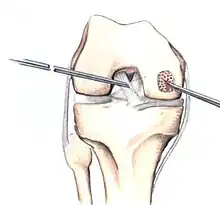

The articular cartilage along the border of the osteochondritis dissecans lesion -

Arthroscopic image of OATS surgery on the medial femoral condyle of the knee

Intact lesions

If non-surgical measures are unsuccessful, drilling may be considered to stimulate healing of the subchondral bone. Arthroscopic drilling may be performed by using an antegrade (from the front) approach from the joint space through the articular cartilage, or by using a retrograde (from behind) approach through the bone outside of the joint to avoid penetration of the articular cartilage. This has proven successful with positive results at one-year follow-up with antegrade drilling in nine out of eleven teenagers with the juvenile form of OCD,[53] and in 18 of 20 skeletally immature people (follow-up of five years) who had failed prior conservative programs.[54]